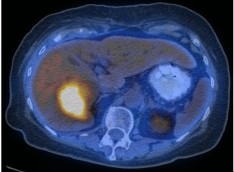

A 71 year-old female presented with an incidental finding of a right hepatic lobe mass, which was hypovascular on contrast-enhanced CT.Images

Axial non-contrast CT (A) and fused PET/CT (B) images through the upper abdomen.